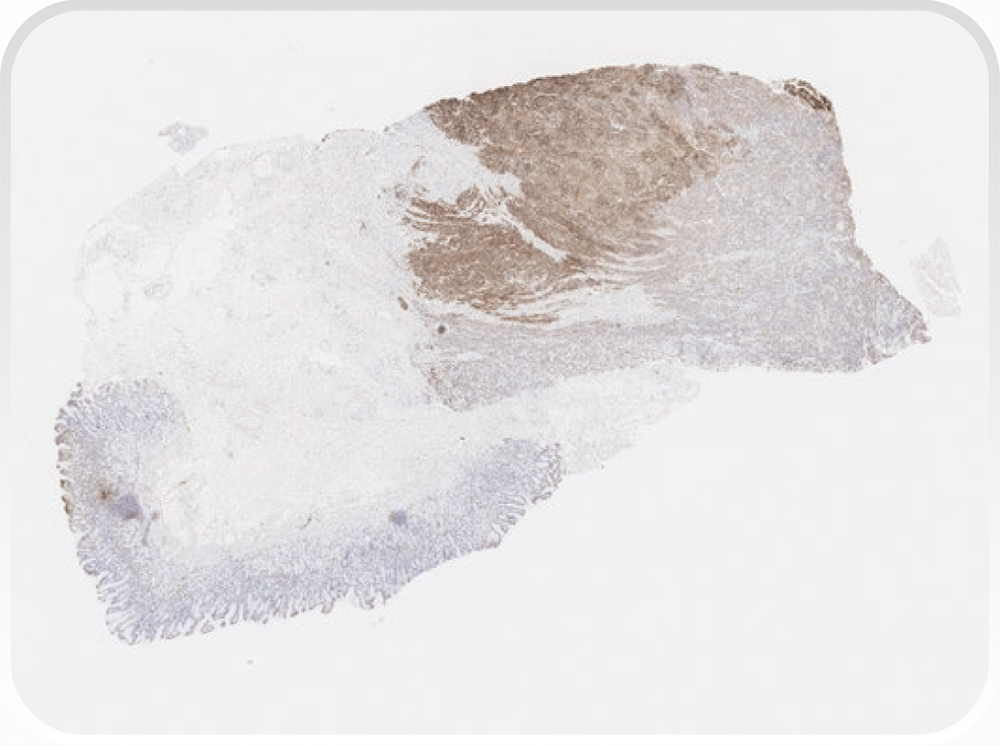

PD-L1の発現状況の指標であるCPSは、PD-L1を発現しているがん細胞及びリンパ球やマクロファージといった免疫細胞をカウントし、その数をがん細胞の総数で除し100を乗じることで算出されます。CPSはTPSと異なり、浸潤癌巣で判定します。

CPSの算出には、以下に示す計算式を用います。

CPSはTPSと異なり、浸潤癌巣で判定します。

①染色陽性細胞が認められる領域におけるCPSを算出する。

※:腫瘍細胞、リンパ球、マクロファージを含む

②すべての腫瘍領域におけるCPSを算出する(染色陽性細胞が認められる領域が全体を占める割合を除する)。

①陽性細胞数が等しくなるように腫瘍領域を複数の領域に分け、各領域におけるCPSを算出する。

②分けた領域数を考慮してCPSを算出する(本例は4領域に分けられている)。